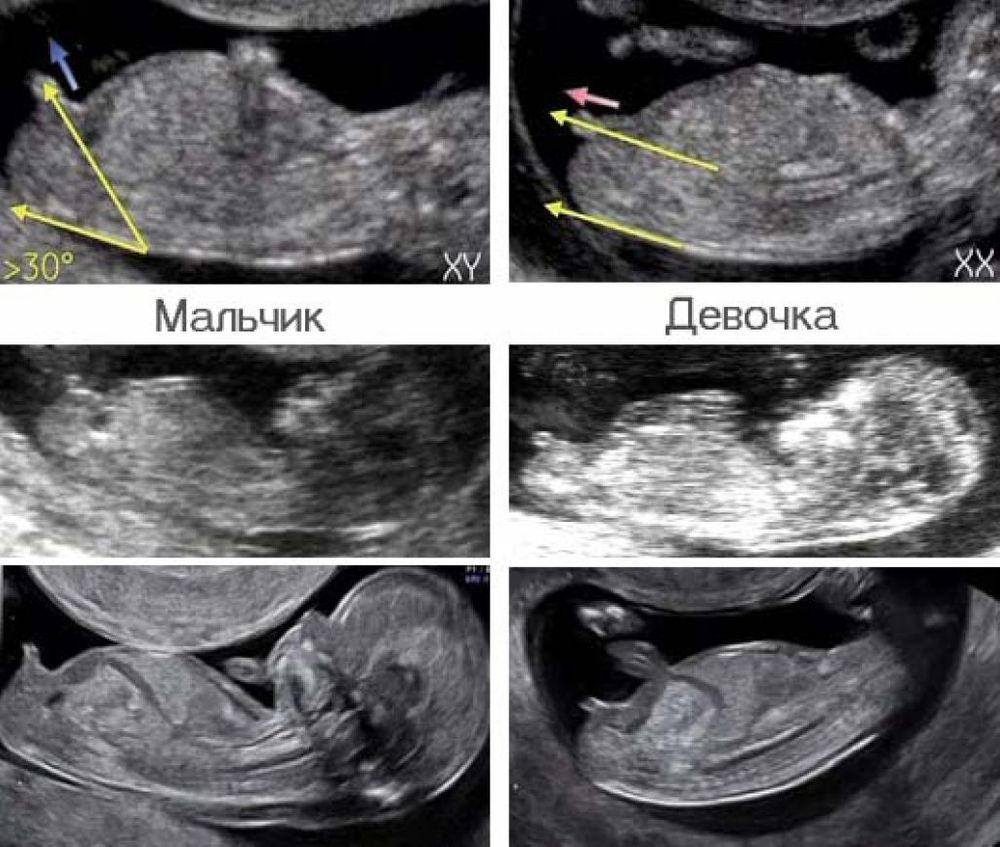

На таком сроке и девочки, и мальчики выглядят практически одинаково😊 Как Вам врач показывал не знаю, но если в профиль по половому бугорку, то молодец.

Юлия Sonnце, мне тоже врач на 1 скрининге все показал и рассказал. Отличаются они как не крути. Сравните фото мальчиков и девочек.

Юлия Sonnце, ну отличаются ведь) писун сложно с чем-то перепутать

Мария Гольдман, конечно. Я ведь не спорю, что не отличаются, но выглядят почти одинаково, если смотреть невооружённым глазом. "Палочка" есть и у тех, и у других (не писюн, а бугорок), которая позже станет пенисом либо клитором. Я только по наклону полового бугорка вижу, например 😊 А уж рассмотреть подробности, что где вырастет - это высший пилотаж, скажем так.

Нюта , показалось. Я говорю о том, что у Вас супер-профессионал врач 😊 Я сама могу только по наклону полового бугорка понять, кто будет, если фото качественное. Ну, как здесь, например.

Юлия Sonnце, на дтой фотке еще сложно отличить даже по наклону, я бы не смогла, а вот есть мамочки скидывают фото девочек и мальчиков там очень отличается. У девочек длиннее и прям параллельно позвоночнику, а у мальчиков выше и торчит короткий писун)

Мария Гольдман, я знаю. Сама не раз тут предполагала желающим😊 Но мне и на этих фото понятно тоже.